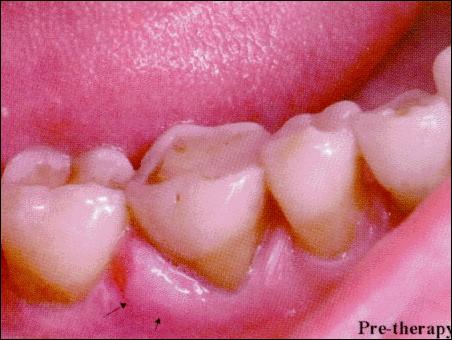

牙周膿腫圖片

下牙內(nèi)側(cè)極易長牙結(jié)石